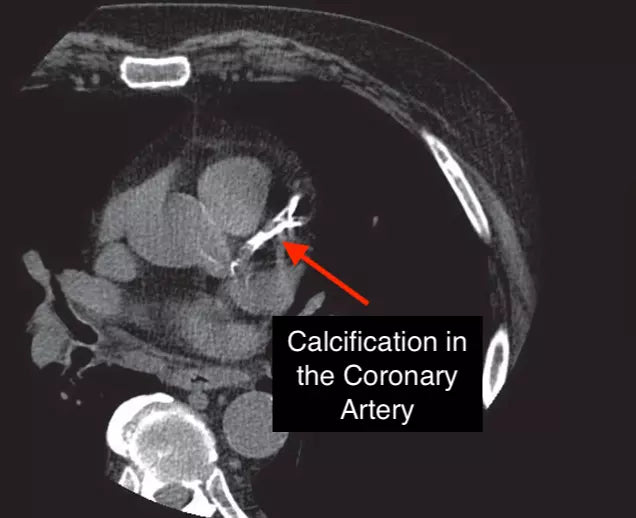

A CT scan that measures calcium in your heart’s arteries, the CAC test helps you see how much plaque is already there—offering insights that can predict future heart attack risk more clearly than many traditional risk factors.